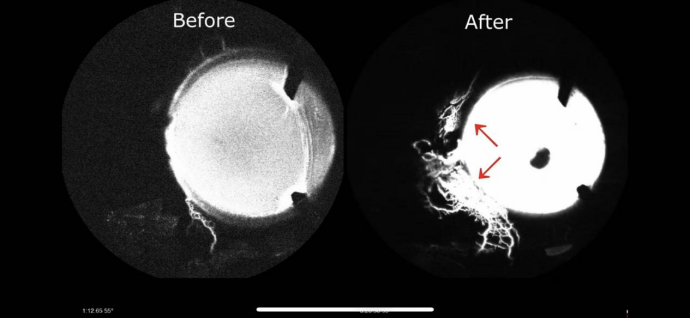

iStent inject W手术前后动态房水造影(厂家供图)

研究显示,超90%的患者在植入iStent后眼压获得良好控制,显著减少术后抗青光眼药物使用。